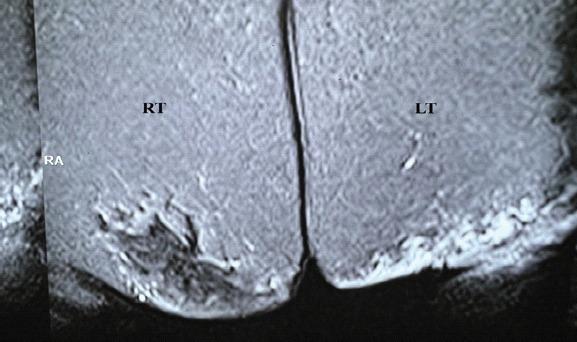

This article reports the case of a 43-year-old woman that came into the orthopedic outpatient department with a history of two masses, one on each buttock. The patient had a history of surgical excision of adiponecrotic mass from the right knee a year back. All the three masses appeared around the same time. Ultrasonography was done to surgically excise the left gluteal mass. The histopathology of the excised mass then confirmed subcutaneous fat necrosis.

本文报告了一名43岁女性的病例,该患者因双侧臀部各有一个肿块的病史前来骨科门诊就诊。患者一年前有过右膝脂肪坏死性肿块手术切除史。所有这三个肿块几乎同时出现。对左侧臀部肿块进行了超声检查以便手术切除。切除肿块的组织病理学检查随后证实为皮下脂肪坏死。